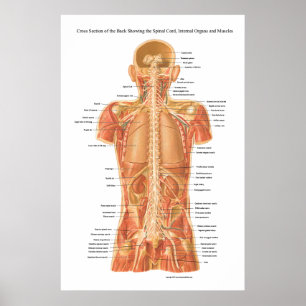

Póster Anatomia do sofrimento

Preço73,50 €